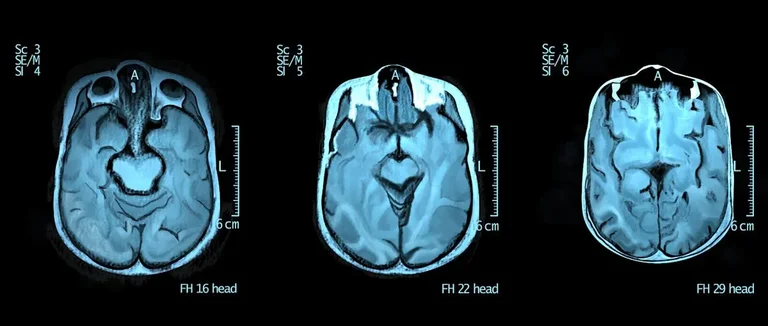

L'Imagerie par Résonance Magnétique (IRM)

L'Imagerie par Résonance Magnétique (IRM) est non invasive. Elle utilise des champs magnétiques pour créer des images détaillées du cerveau. L'IRM est très utile pour voir les anomalies structurelles, comme les lésions.

La Tomographie par Émission Monophotonique (SPECT) évalue l'activité cérébrale. Elle détecte des radiotraceurs injectés dans le corps. La SPECT observe le fonctionnement du cerveau et trouve les zones d'activité anormale.

Les images du scanner, comme la SPECT, montrent l'activité du cerveau. Des zones plus ou moins actives peuvent signaler des problèmes.

Par exemple, des études montrent que la dépression peut réduire l'activité dans certaines zones du cerveau.